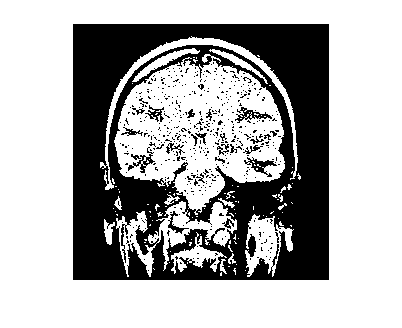

Загрузите 3-D объемные данные.

load mristack

V = mristack;

Создайте 2D маску для начального переднего плана и фоновых точек seed.

seedLevel = 10;

fseed = V(:,:,seedLevel) > 75;

bseed = V(:,:,seedLevel) == 0;

Отобразите передний план и фоновые точки seed.

imshow(fseed)

imshow(bseed)

Поместите точки seed в пустую 3-D маску.

fmask = zeros(size(V));

bmask = fmask;

fmask(:,:,seedLevel) = fseed;

bmask(:,:,seedLevel) = bseed;

Создайте начальную необходимую область.

roi = false(size(V));

roi(10:end-10,10:end-10,:) = true;

Сгенерируйте матрицу метки.

L = superpixels3(V,500);

Выполните GrabCut.

bw = grabcut(V,L,roi,fmask,bmask);

Отобразите 3D сегментированное изображение.

montage(reshape(bw,size(V)))